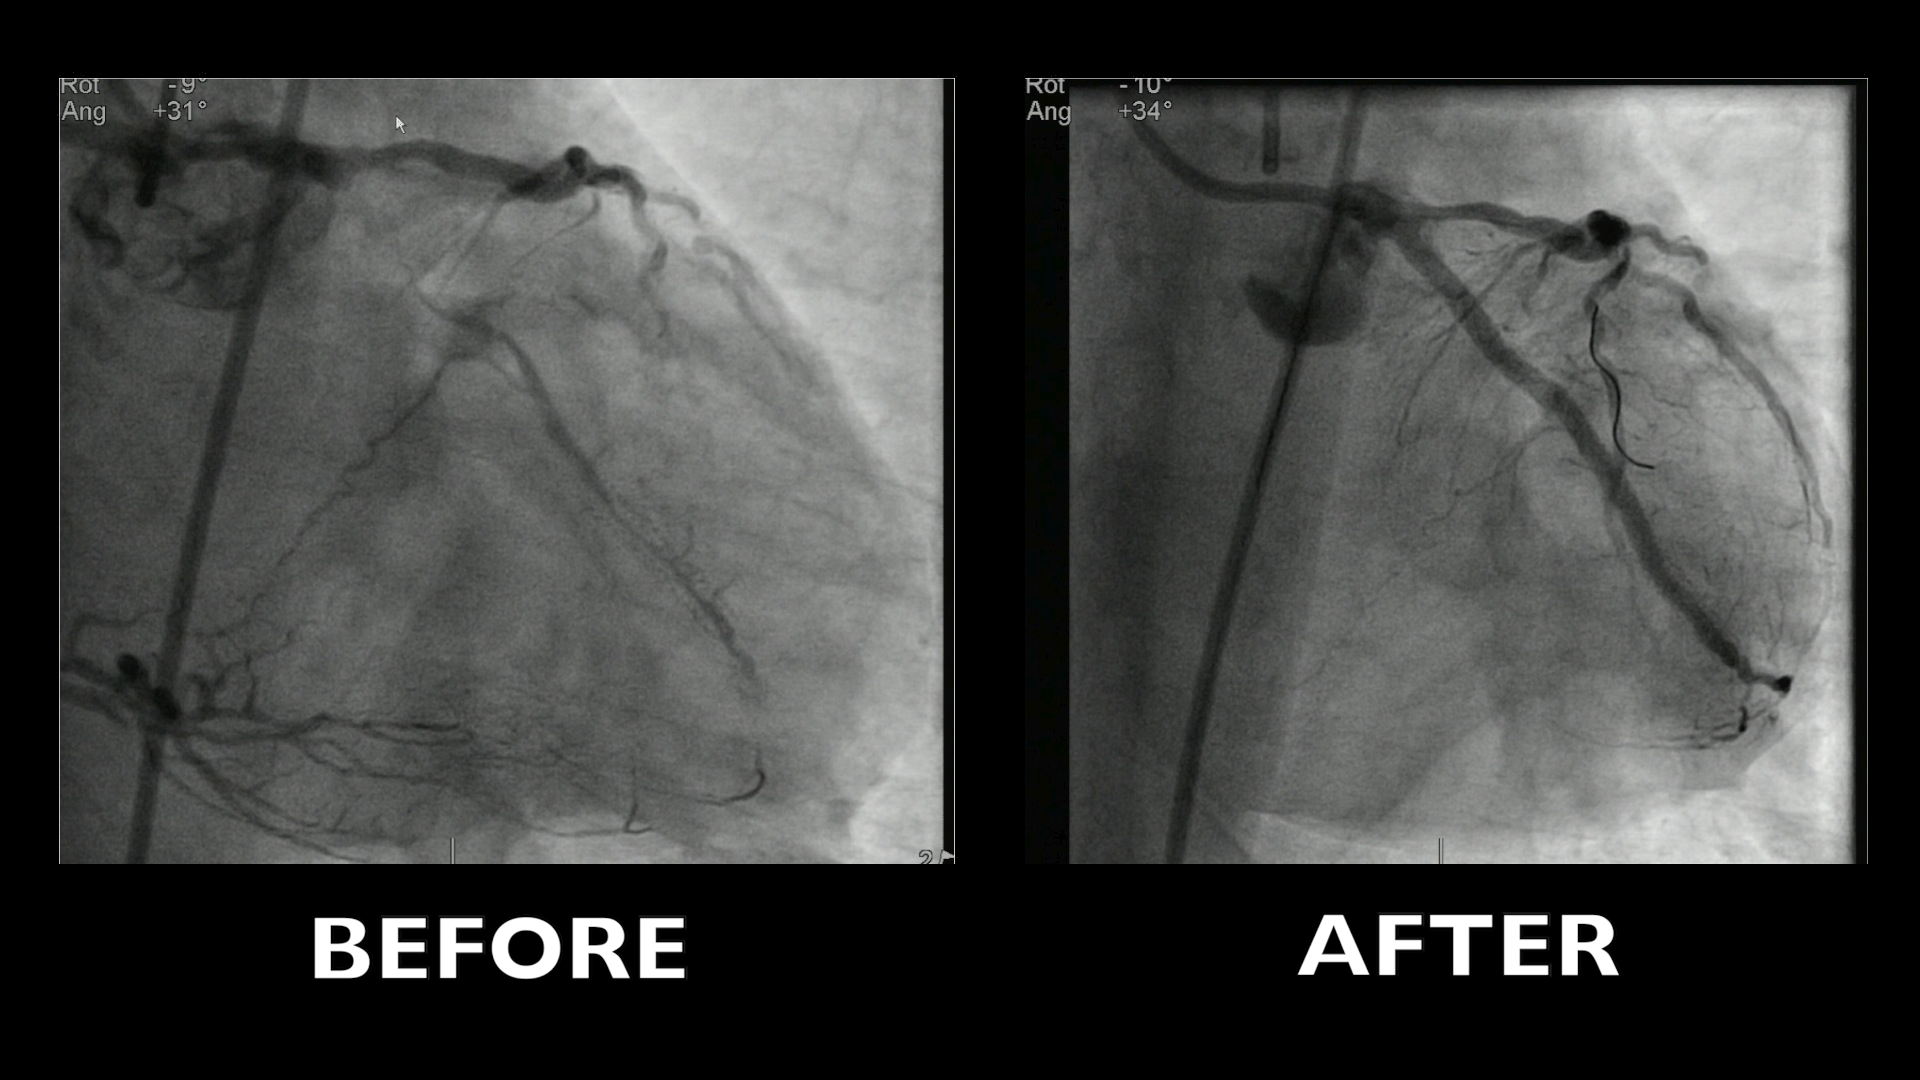

This 40 minutes didactic recorded procedure concerns a symptomatic coronary artery disease patient with a very old long complex mid-RCA occlusion (J-CTO score 4) first attempted retrogradely and then antegradely, using modern strategy and latter tools for coronary artery recanalization.